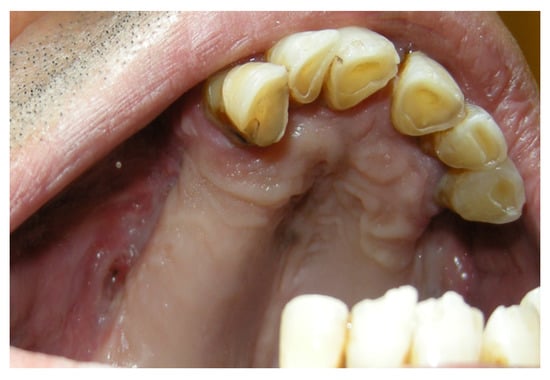

3.1.2. Case 2: P.S.

| P.S. | X | * | 7 | 0 | ||